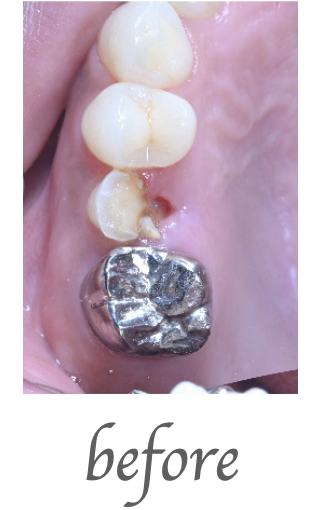

治療内容

右下奥歯の被せの脱離でこられた患者様です。右下の歯の精密根管治療を行いました。

治療期間・回数

治療期間:約2週間 治療回数:3回

費用

¥130,000(税込143,000)

リスク・副作用

処置直後2〜3日は軽微な痛みが出ることがあります。再感染・症状の改善を認めない場合があります。